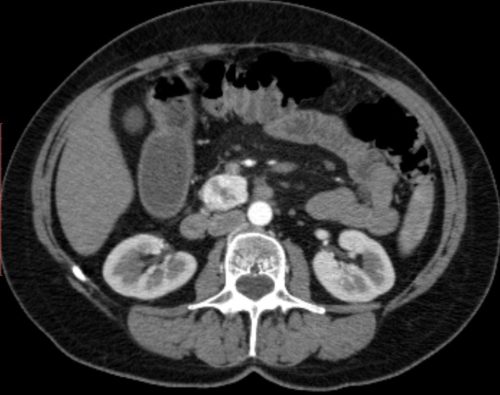

КТ поджелудочной железы

Что такое и что показывает КТ поджелудочной железы

SQLITE NOT INSTALLED КТ поджелудочной железы – способ диагностики, позволяющий производить визуализацию строения органа. Метод построен на принципах сканирования органов и тканей рентгеновскими лучами и последующей обработки полученных данных. Способ довольно быстрый, сканирование занимает около 10 минут и меньше. КТ позволяет определить заболевания артерий для выяснения степени воспалительного поражения органа. Такое обследование позволяет получать снимки …